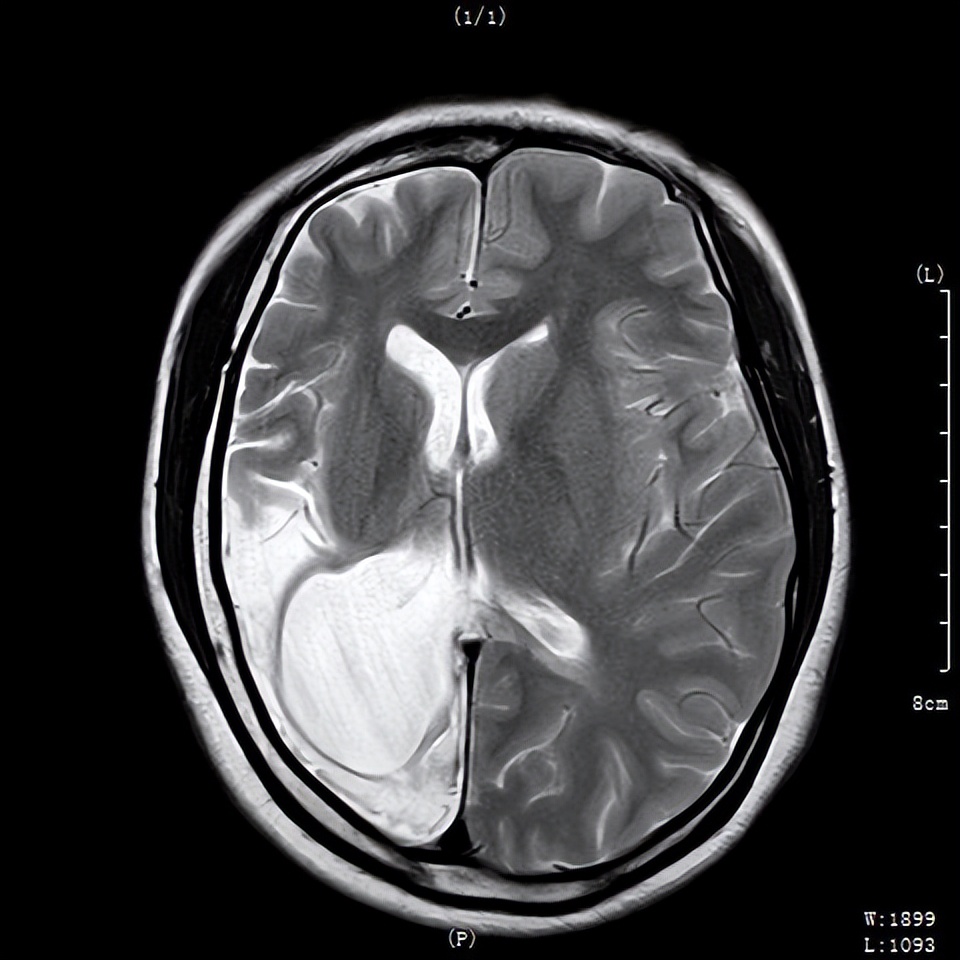

2020年,术后2年复查时核磁共振检查

完善脑电图检测、头颅核磁共振(MRI)、wada实验等全面检查后,脑电图结果提示:脑内存在癫痫样放电,且右侧大脑半球放电明显;MRI结果提示:右海马硬化,右侧大脑半球萎缩,考虑为致痫灶可能;wada试验结果提示:双侧肢体运动、语言、感觉等功能为左侧半球支配,考虑右侧大脑半球基本无功能,被左侧大脑带代偿。

术后出院时核磁共振检查